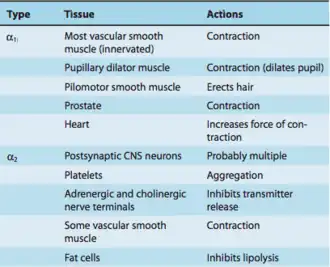

There are several α receptors throughout the body where these drugs can bind. Specifically, α1 receptors can be found in most vascular smooth muscle, the pupillary dilator muscle, the heart, the prostate, and pilomotor smooth muscle.[2] On the other hand, α2 receptors can be found in platelets, cholinergic nerve terminals, some vascular smooth muscle, postsynaptic CNS neurons, and fat cells.[2]

The structure of α receptors is a classic G protein–coupled receptors (GPCRs) consisting of 7 transmembrane domains, which form three intracellular loops and three extracellular loops.[2] These receptors couple to heterotrimeric G proteins composed of α, β, and γ subunits.[2] Although both of the α receptors are GPCRs, there are large differences in their mechanism of action. Specifically, α1 receptors are characterized as Gq GPCRs, signaling through Phospholipase C to increase IP3 and DAG, thus increasing the release of calcium. Meanwhile, α2 receptors are labeled as Gi GPCRs, which signal through adenylyl cyclase to decrease cAMP.[38]

Because the α1 and α2 receptors have different mechanisms of action, their antagonists also have different effects.[39] α1 blockers can inhibit the release of IP3 and DAG to decrease calcium release, thus, decreasing overall signaling. On the other hand, α2 blockers prevent the reduction of cAMP, thus leading to an increase in overall signaling.